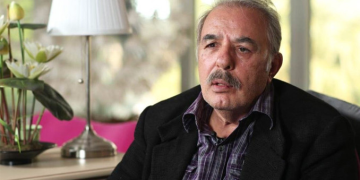

Ankara Etlik Kent Hastanesi Bayan ve Doğum Hastanesi Başhekimi Doç. Dr. Çağanay Soysal, yaptığı açıklamada, sıcak havaların bilhassa gebeleri ve bebekleri etkilediğini söyleyerek, “Yüksek ateş, nabız artışı, sıvı kaybı, mide bulantısı, baş dönmesi ve ağrısı, halsizlik, yorgunluk ve kramplar sıcak çarpmasının belirtileri ortasında yer alır. Çok terlemeye bağlı dehidrasyon dediğimiz sıvı kaybı tansiyon düşmesine yol açabilir. Tansiyon düşmesi de hamilelerde baş dönmesi ve bayılma şikayetleri ile karşımıza çıkabilir. Maalesef bunlar da istenmeyen kazalara, hamilelerin düşüp yaralanmasına, anne ve bebek sıhhatini tehdit eden mümkün komplikasyonların ortaya çıkmasına sebep olabilir” dedi.

Gebelerin en çok ‘denize ve havuza girebilir miyiz’ sorusunun yanıtını aradığını vurgulayan Soysal, kelamlarına şöyle devam etti: